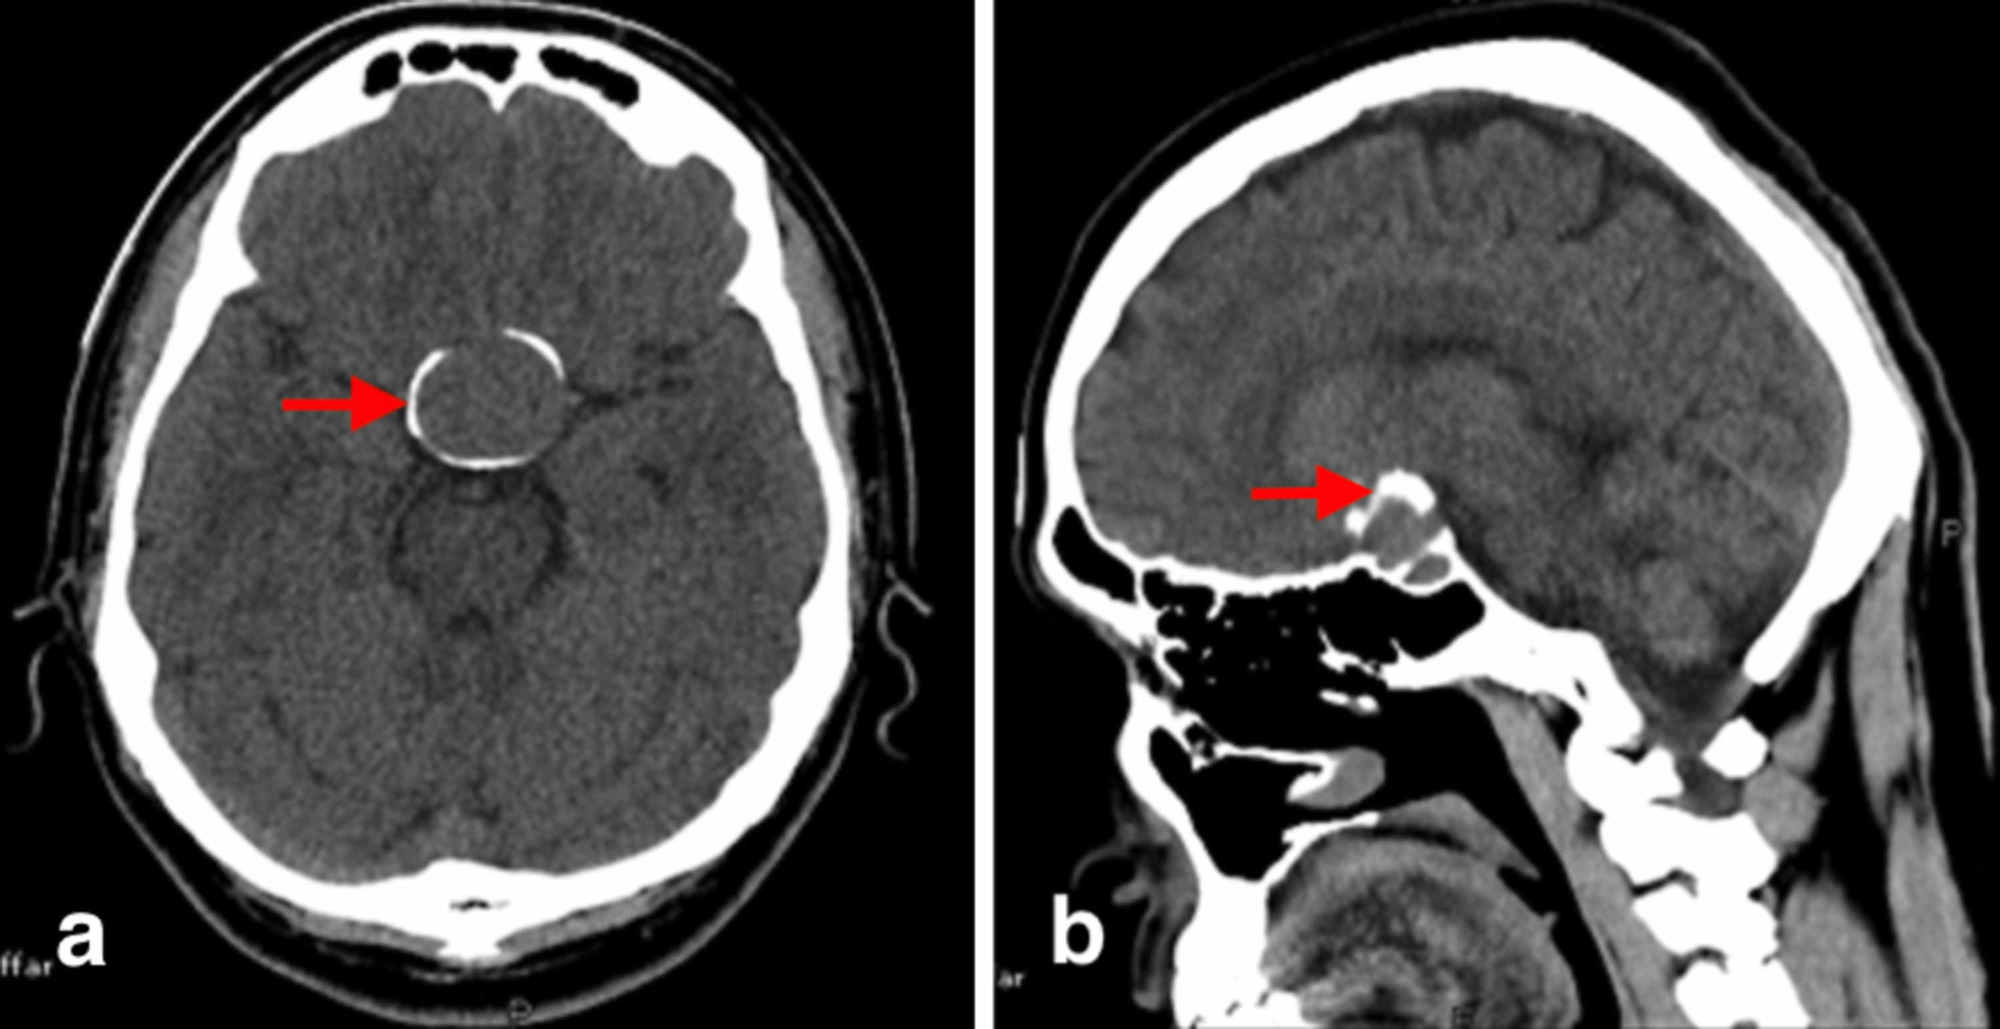

Brain (Adult

Anatomic region: Brain

Positioning Supine, (IOM ) parallel to x-ray beam, head first.

Scout view: AP and lateral, length (150-250) mm, Angle 0 degree.

Scan area from foramen magnum to vertex.

Contrast media

IV: if indicated 50 e.c

Oral : No

Rectal No

Injection rate 20 c.c /sec

Scan delay time :(1-2 min)

Scan type axial, slice thickness ( 2.5 mm post fossa and 7.5 brain tissue)

Viewing ( photography) S.T ( 150-75 ww) - ( 35-50 wl), B.W (1300-2000 ww ) ( 300-500 wl)

- Reconstruction : if needed

Sag: yes

Cor : yes

Axial:

3D display : yes

Special instruction : Raw data must be saved.

- Remarks:

1- call patient don't move.

2- remove all metal thing from scan area

3-bone window is necessary in trauma cases R/O fracture in malignancy tumors R/O bone defect.